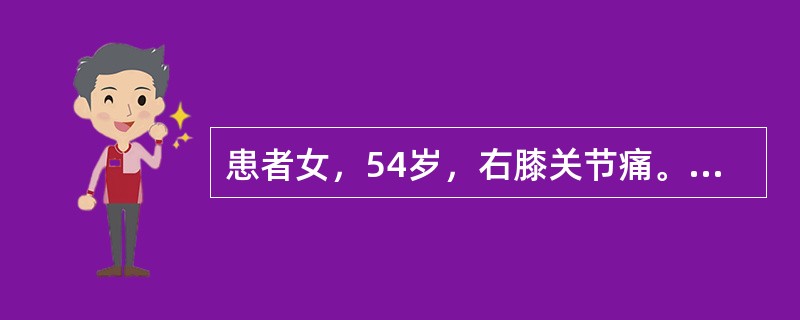

患者女,54岁,右膝关节痛。实验室检查:类风湿因子阳性,除外膝关节类风湿性关节炎。X线检查结果如下图。

MRI结果如下图,诊断应为

MRI结果如下图,诊断应为

A.膝关节退行性骨关节炎

B.膝关节类风湿性关节炎

C.膝关节色素沉着绒毛结节性滑膜炎

D.膝关节滑膜型结核

E.血清阴性脊椎关节炎膝关节侵犯